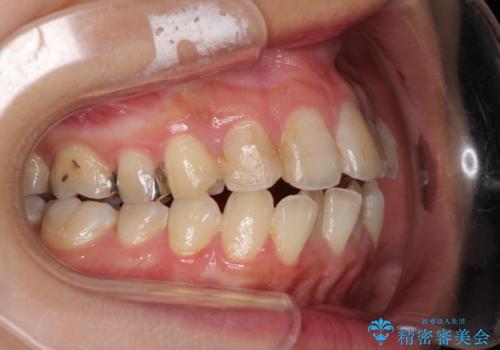

後戻りを治したい 骨格的なズレの大きい方のインビザライン矯正

- 中学生の時に矯正治療をしたものの、後戻りを気にして来院された患者様です。

骨格的に下顎が右側に変位しているため、左右の咬み合わせを理想的なものに改善することはできませんが、インビザラインにて歯列を整えることとしました。

骨格的なズレによる左右差は改善できませんでしたが、上下の正中を極力合わせるようにすることができました。